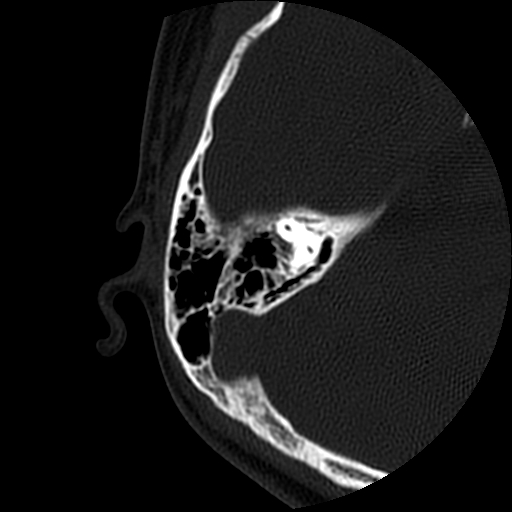

以下是引用随光逐影在2009-8-19 7:25:00的发言:[br]右侧慢性中耳乳突炎,右侧中耳腔及外耳道肉芽肿或胆脂瘤形成。